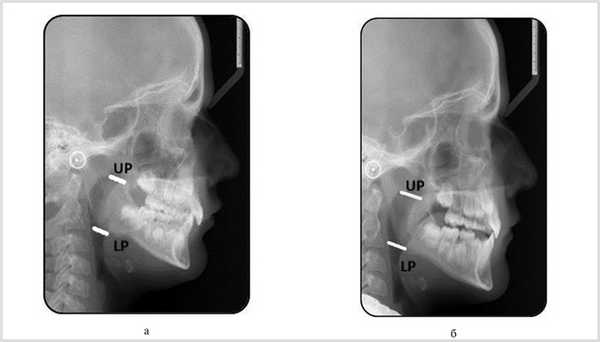

ТРГ проводилась до и после ортодонтического лечения на ортопантомографе Orthophos XG, XG Plus/Ceph при стандартном положении головы в цефалостате, т. е. вертикально без компенсаторного прогиба в шейном отделе, что обеспечивало истинную картину расположения нижней челюсти (НЧ) и языка. Ширину просвета (переднезадний размер) дыхательных путей оценивали по ширине просвета носо- и ротоглотки в верхнем и нижнем ее отделах методом MacNamara [1]. Ширина просвета верхнего фарингеального (UP) пространства определяется от наиболее задней точки на поверхности мягкого неба до ближайшей точки задней стенки глотки. За норму было принято расстояние 15—20 мм. Ширина нижнего фарингеального (LP) пространства измерялась от точки пересечения задней границы языка и края НЧ до ближайшей точки на задней стенки глотки (рис. 1). Норма составляла 11—14 мм в возрасте от 7 до 9 лет.

Рис. 1. ТРГ. а — нормальный переднезадний размер дыхательных путей; б — уменьшенный; UP — верхнее фарингеальное пространство; LP — нижнее фарингеальное пространство.

На ТРГ детей после ортодонтического лечения наблюдалось достоверное увеличение (рис. 3) проходимости верхних и нижних фарингеальных воздушных путей (табл. 1: F — условный коэффициент, соотношение UP к LP). Через 2 года ортодонтического лечения коэффициент F у девочек был равен 1,15, у мальчиков — 1,13.

Рис. 3. Пациентка К., 9 лет; история болезни № 0047118; нижняя ретрогнатия; дистальная окклюзия; глубокая резцовая окклюзия. Скученность зубов; ТРГ в боковой проекции. Величина верхнего (UP) и нижнего (LP) фарингеального пространства. а — до ортодонтического лечения: UP и LP; б — после лечения: UP и LP.